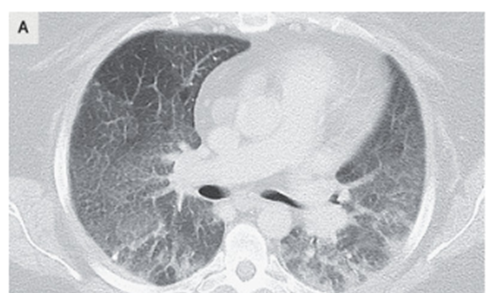

喫煙関連特発性間質性肺炎(剥離性間質性肺炎、DIP:desquamative interstitial pneumonia):たばこを吸うとなる間質性肺炎

34歳女性。労作時呼吸困難と空咳が悪化傾向のため内科外来を受診した。 既往は特になく、職場も特に変化なし。薬物使用なし。発熱も特になかった。喫煙あり。 来院時 …